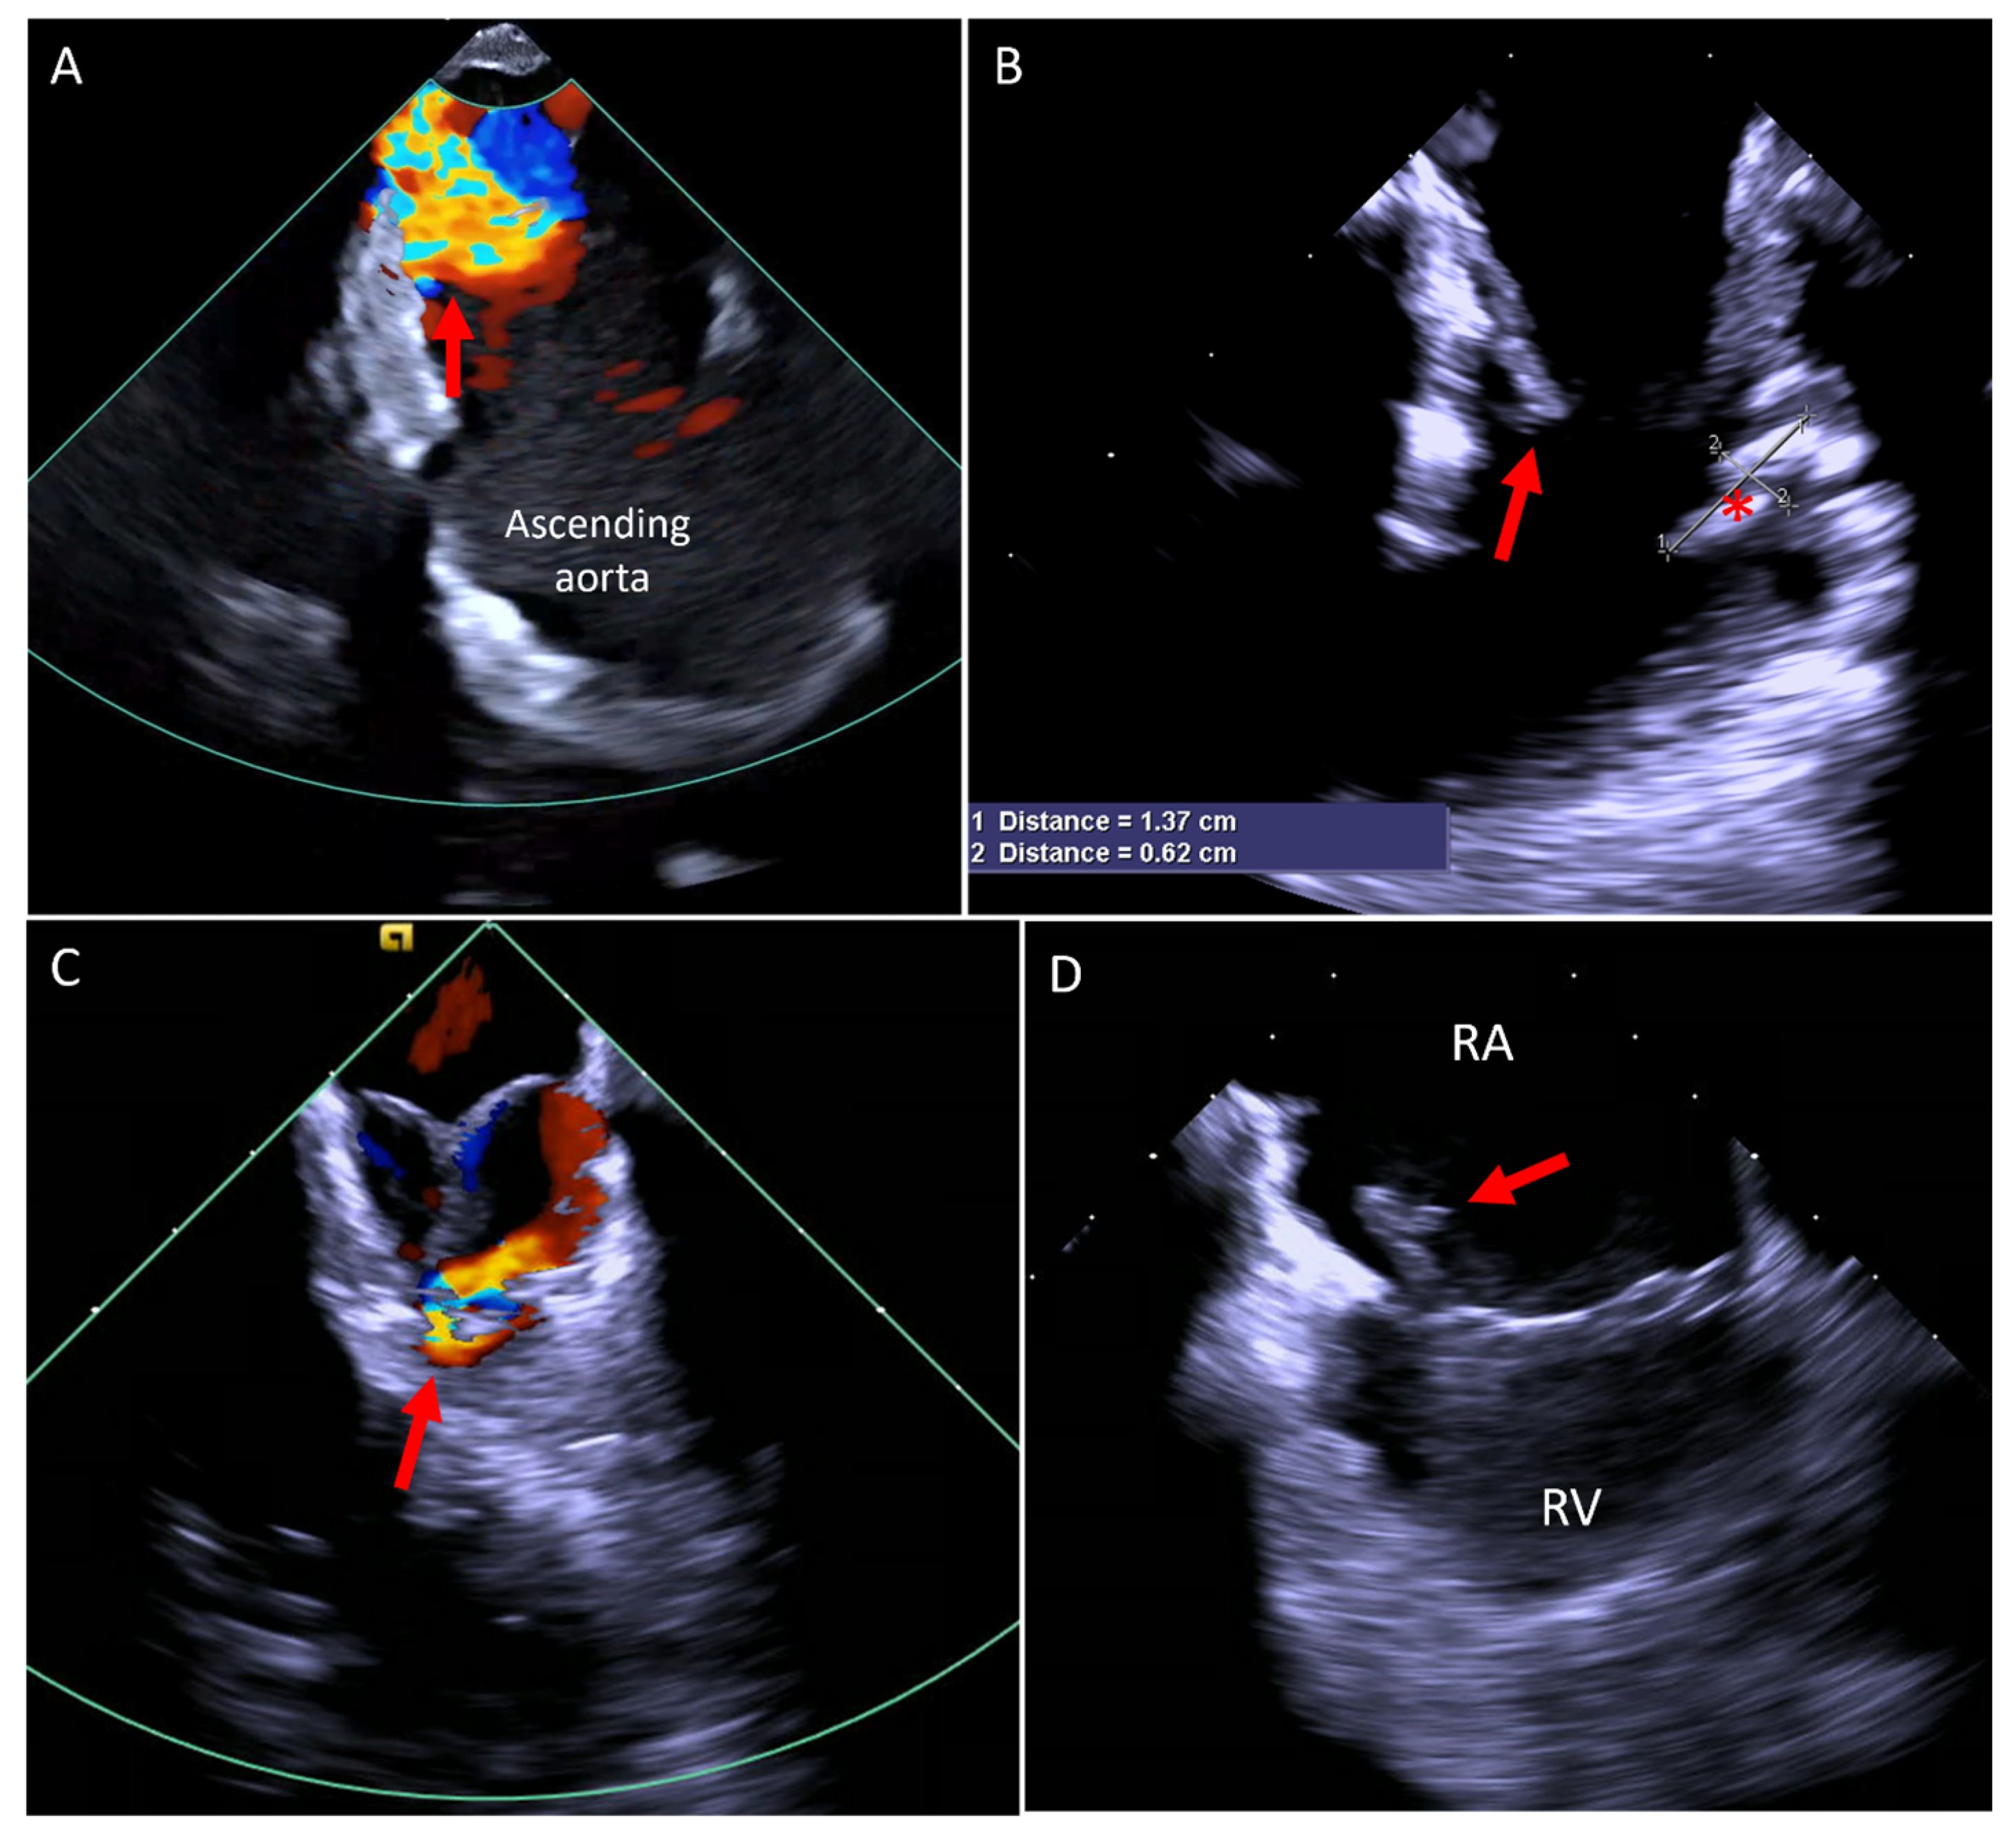

5.3. Transcatheter Pulmonary Valve Replacement (TCPVR)